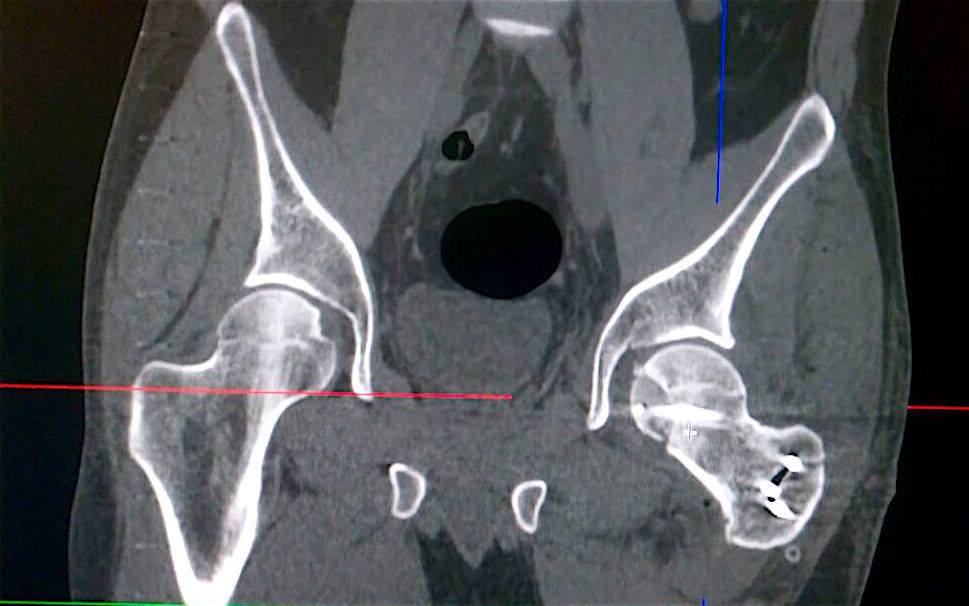

Травматический вывих левого бедра с переломом головки бедренной кости

Травматический вывих левого бедра с переломом головки бедренной кости, произведено открытое вправление, репозиция перелома головки бедренной кости с применением костной аллопластики материалом «Лиопласт».